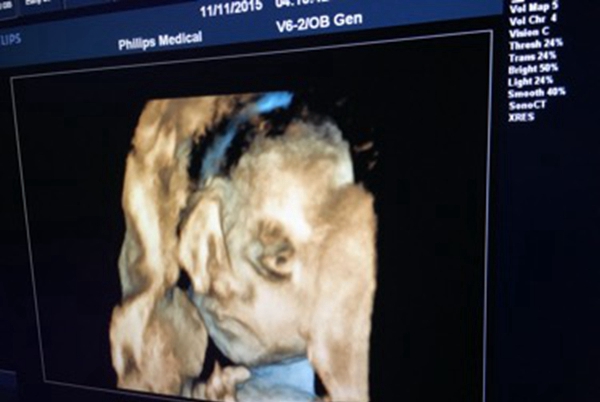

女子生出无眼婴儿 什么会引导胎儿没眸子

导语:普遍来说家里核心有新性命出身是一件很痛快的事务,然而是广州别名女子生下儿童却不那么让人喜悦,本来儿童从出身起便不睁启眼睛,厥后医生说他患上了无眼症。

女子生出无眼婴儿

天才不眼睛真实很让人懊恼,而无眼症该当是一种比拟少睹的基因疾病,这也是一种反常纵然查过b超也很难创造。博家以为该疾病大概是基因渐变引起的,大概者说妊妇在怀胎初期,胚胎爆发了某些奇异的变革,这些都是没措施阐明的。

儿童也和其余方才方才出身的普遍绚烂,他也会动来动去连交哭闹,除了眼睛除外其余都是平常的。无眼症这个疾病也是很残酷的,天才不眼睛的儿童以来生计真实艰巨得多。

无眼症是一种很少睹的疾病,有着很矮的发病率,一些患儿缺乏局部眼球,有些直交不眼球,这种疾病很难经过B超创造。该患儿家人也说了产妇都保持举行体检,都没创造什么不关于劲的,没料到儿童会如许。